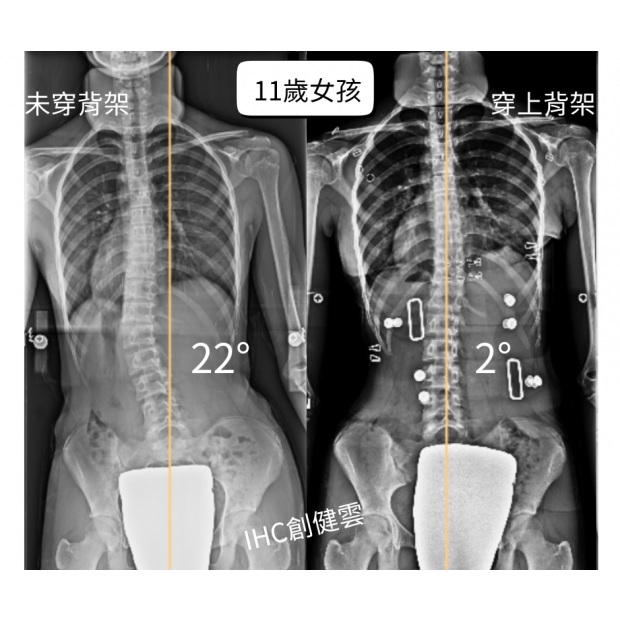

11歲脊椎側彎女孩,腰彎22度

11歲脊椎側彎女孩,腰彎22度 穿上背架後立即矯正效果